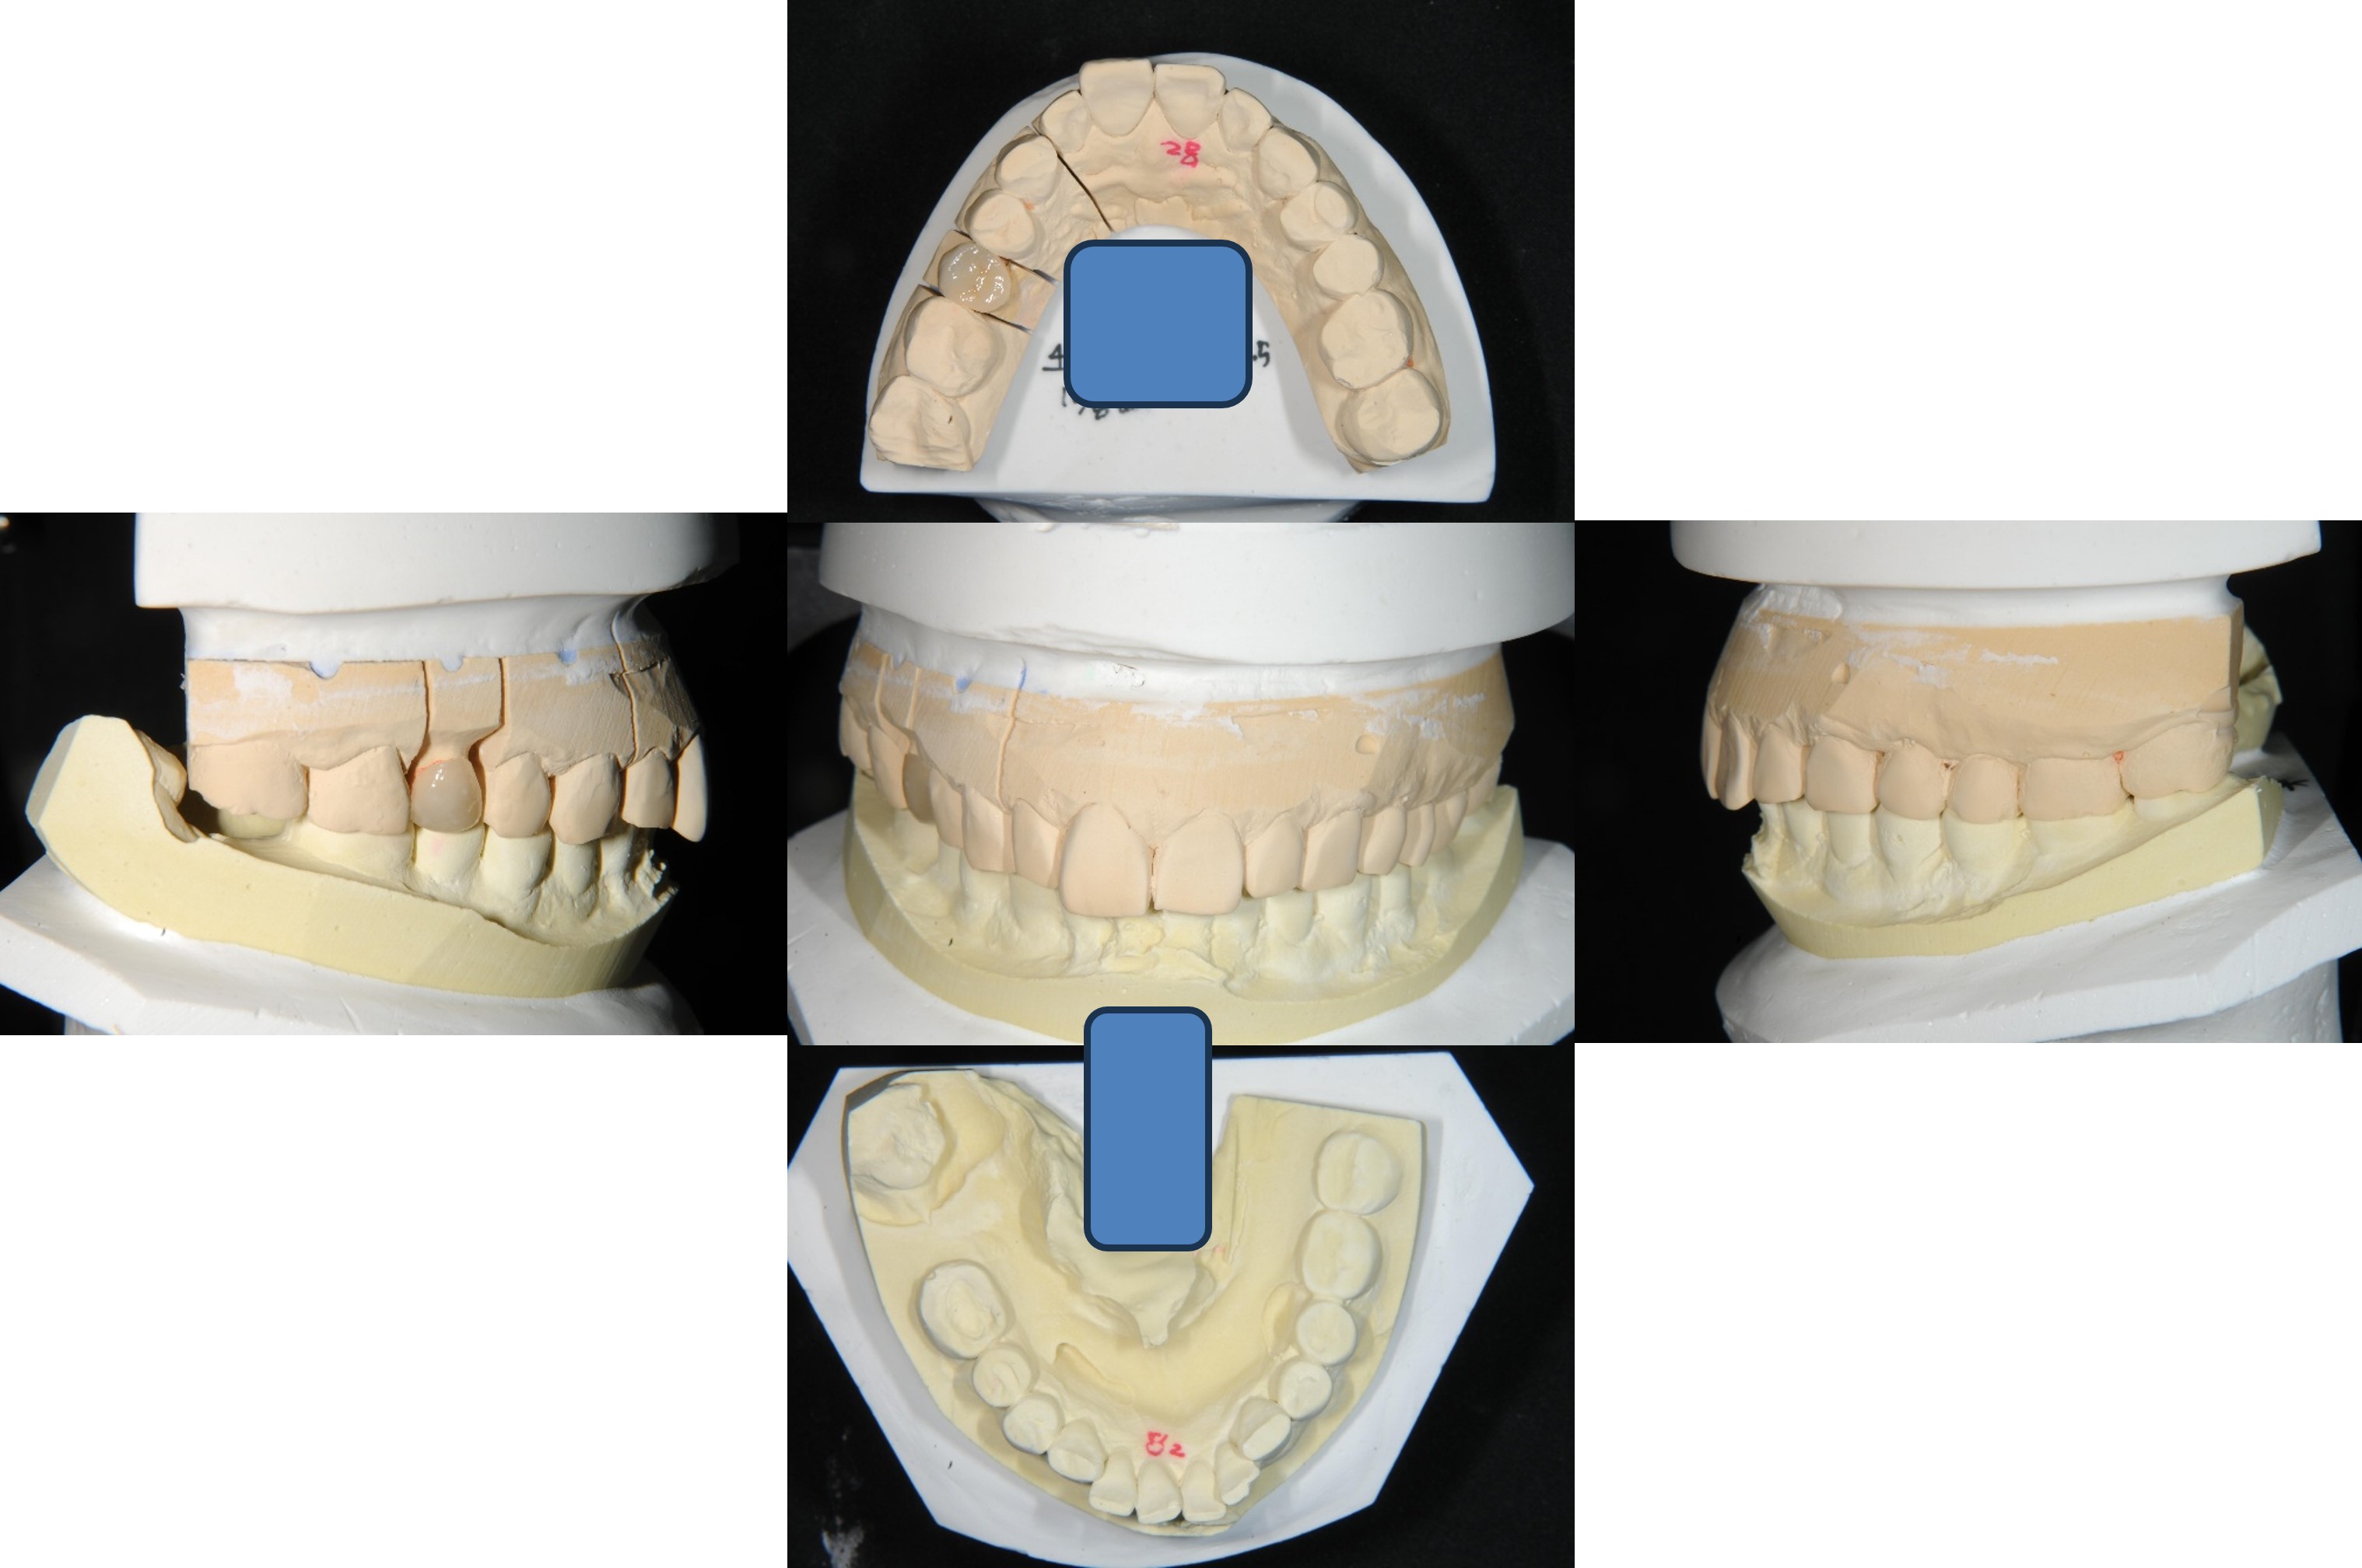

印模後,上咬合器

模型製作

陶瓷冠塊體